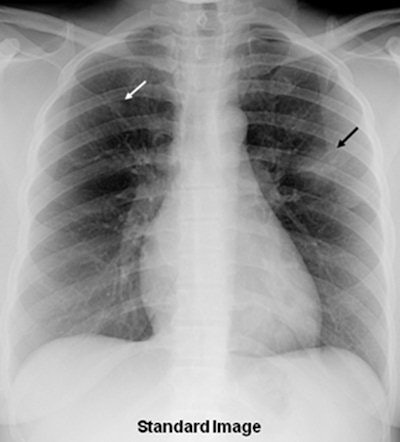

A 36-year-old woman with focal pneumonia. Top: Portable chest radiograph shows focal airspace opacity in left upper lobe and a very small nodule in right upper lobe (arrows). Above: Bone suppression image shows these airspace opacities more clearly. Below: Coronal reconstruction from CT scan performed five days later. The right opacity had resolved and the left opacity had decreased on the follow-up CT. All images courtesy of Dr. Feng Li.